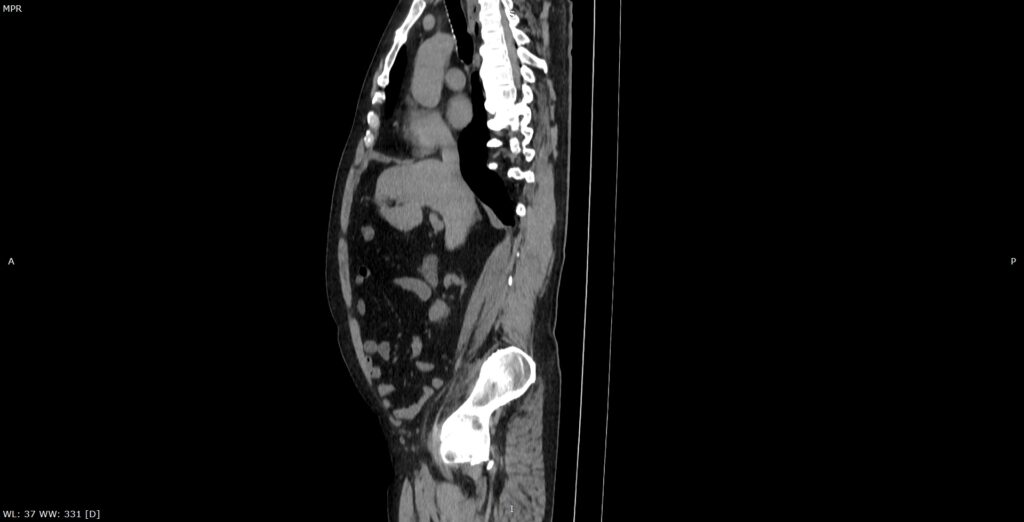

Figura 2: reconstrucție oblic sagitală din achiziție CT fără contrast posttraumatic imediat

Discuţie caz nr 134: Pe imaginile achiziționate fără substanță de contrast se remarcă creștere marcată de volum a muschiului ilio-psoas drept în două treimi distale cu evidențierea unei plaje întinse cu densități sangvine ce sugerează prezența unui hematom posttraumatic; nu se evidențiază traiecte de fractură. Achiziția de control după 22 de luni evidențiază reducerea grosimii corpului muscular ilio-psoas drept cu încărcare grăsoasă care, pe alocuri, afectează aproape complet corpul muscular.